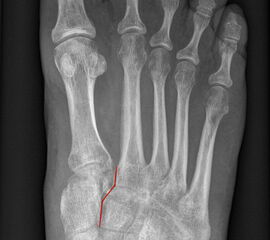

Auf den dp-Aufnahmen sollte der mediale Rand der Metatarsale-2-Basis mit dem medialen Rand des Os cuneiforme intermedium eine homogene Linie ohne Stufenbildung bilden (Abb. 7+8). Außerdem ist auf den Abstand zwischen der Metatarsale-1- und -2-Basis zu achten. Dieser sollte nicht größer als 2 mm bzw. im Vergleich zur Gegenseite nicht mehr als 1 mm erweitert sein. In bis zu 90% der Fälle zeigt sich ein sogenanntes „Fleck sign“ (Abb. 9), ein knöchernes Fragment zwischen der Metararsale-1- und -2-Basis im Sinne eines knöchernen Ausrisses des Lisfranc-Ligaments an der Metatarsale-2-Basis 211936410. Oft liegen zusätzliche Frakturen der Metatarsalebasen oder der Tarsale vor, die ebenfalls identifiziert werden sollten. Bei jeder Mittelfußbasisfraktur sollte umgekehrt an eine Lisfranc-Verletzung gedacht werden.

Zum Lesen der Bildbeschreibung und zur Vollansicht bitte die Bilder anklicken.